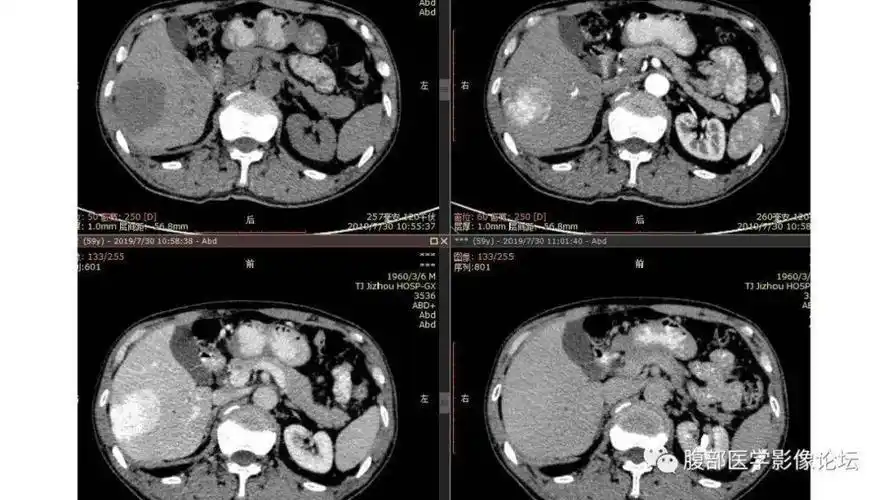

肝血管瘤ct表现

肝脏血管瘤影像学表现及鉴别诊断二影像天地

肝脏血管瘤影像学表现及鉴别诊断(一) | 影像天地

肝脏丨血管瘤